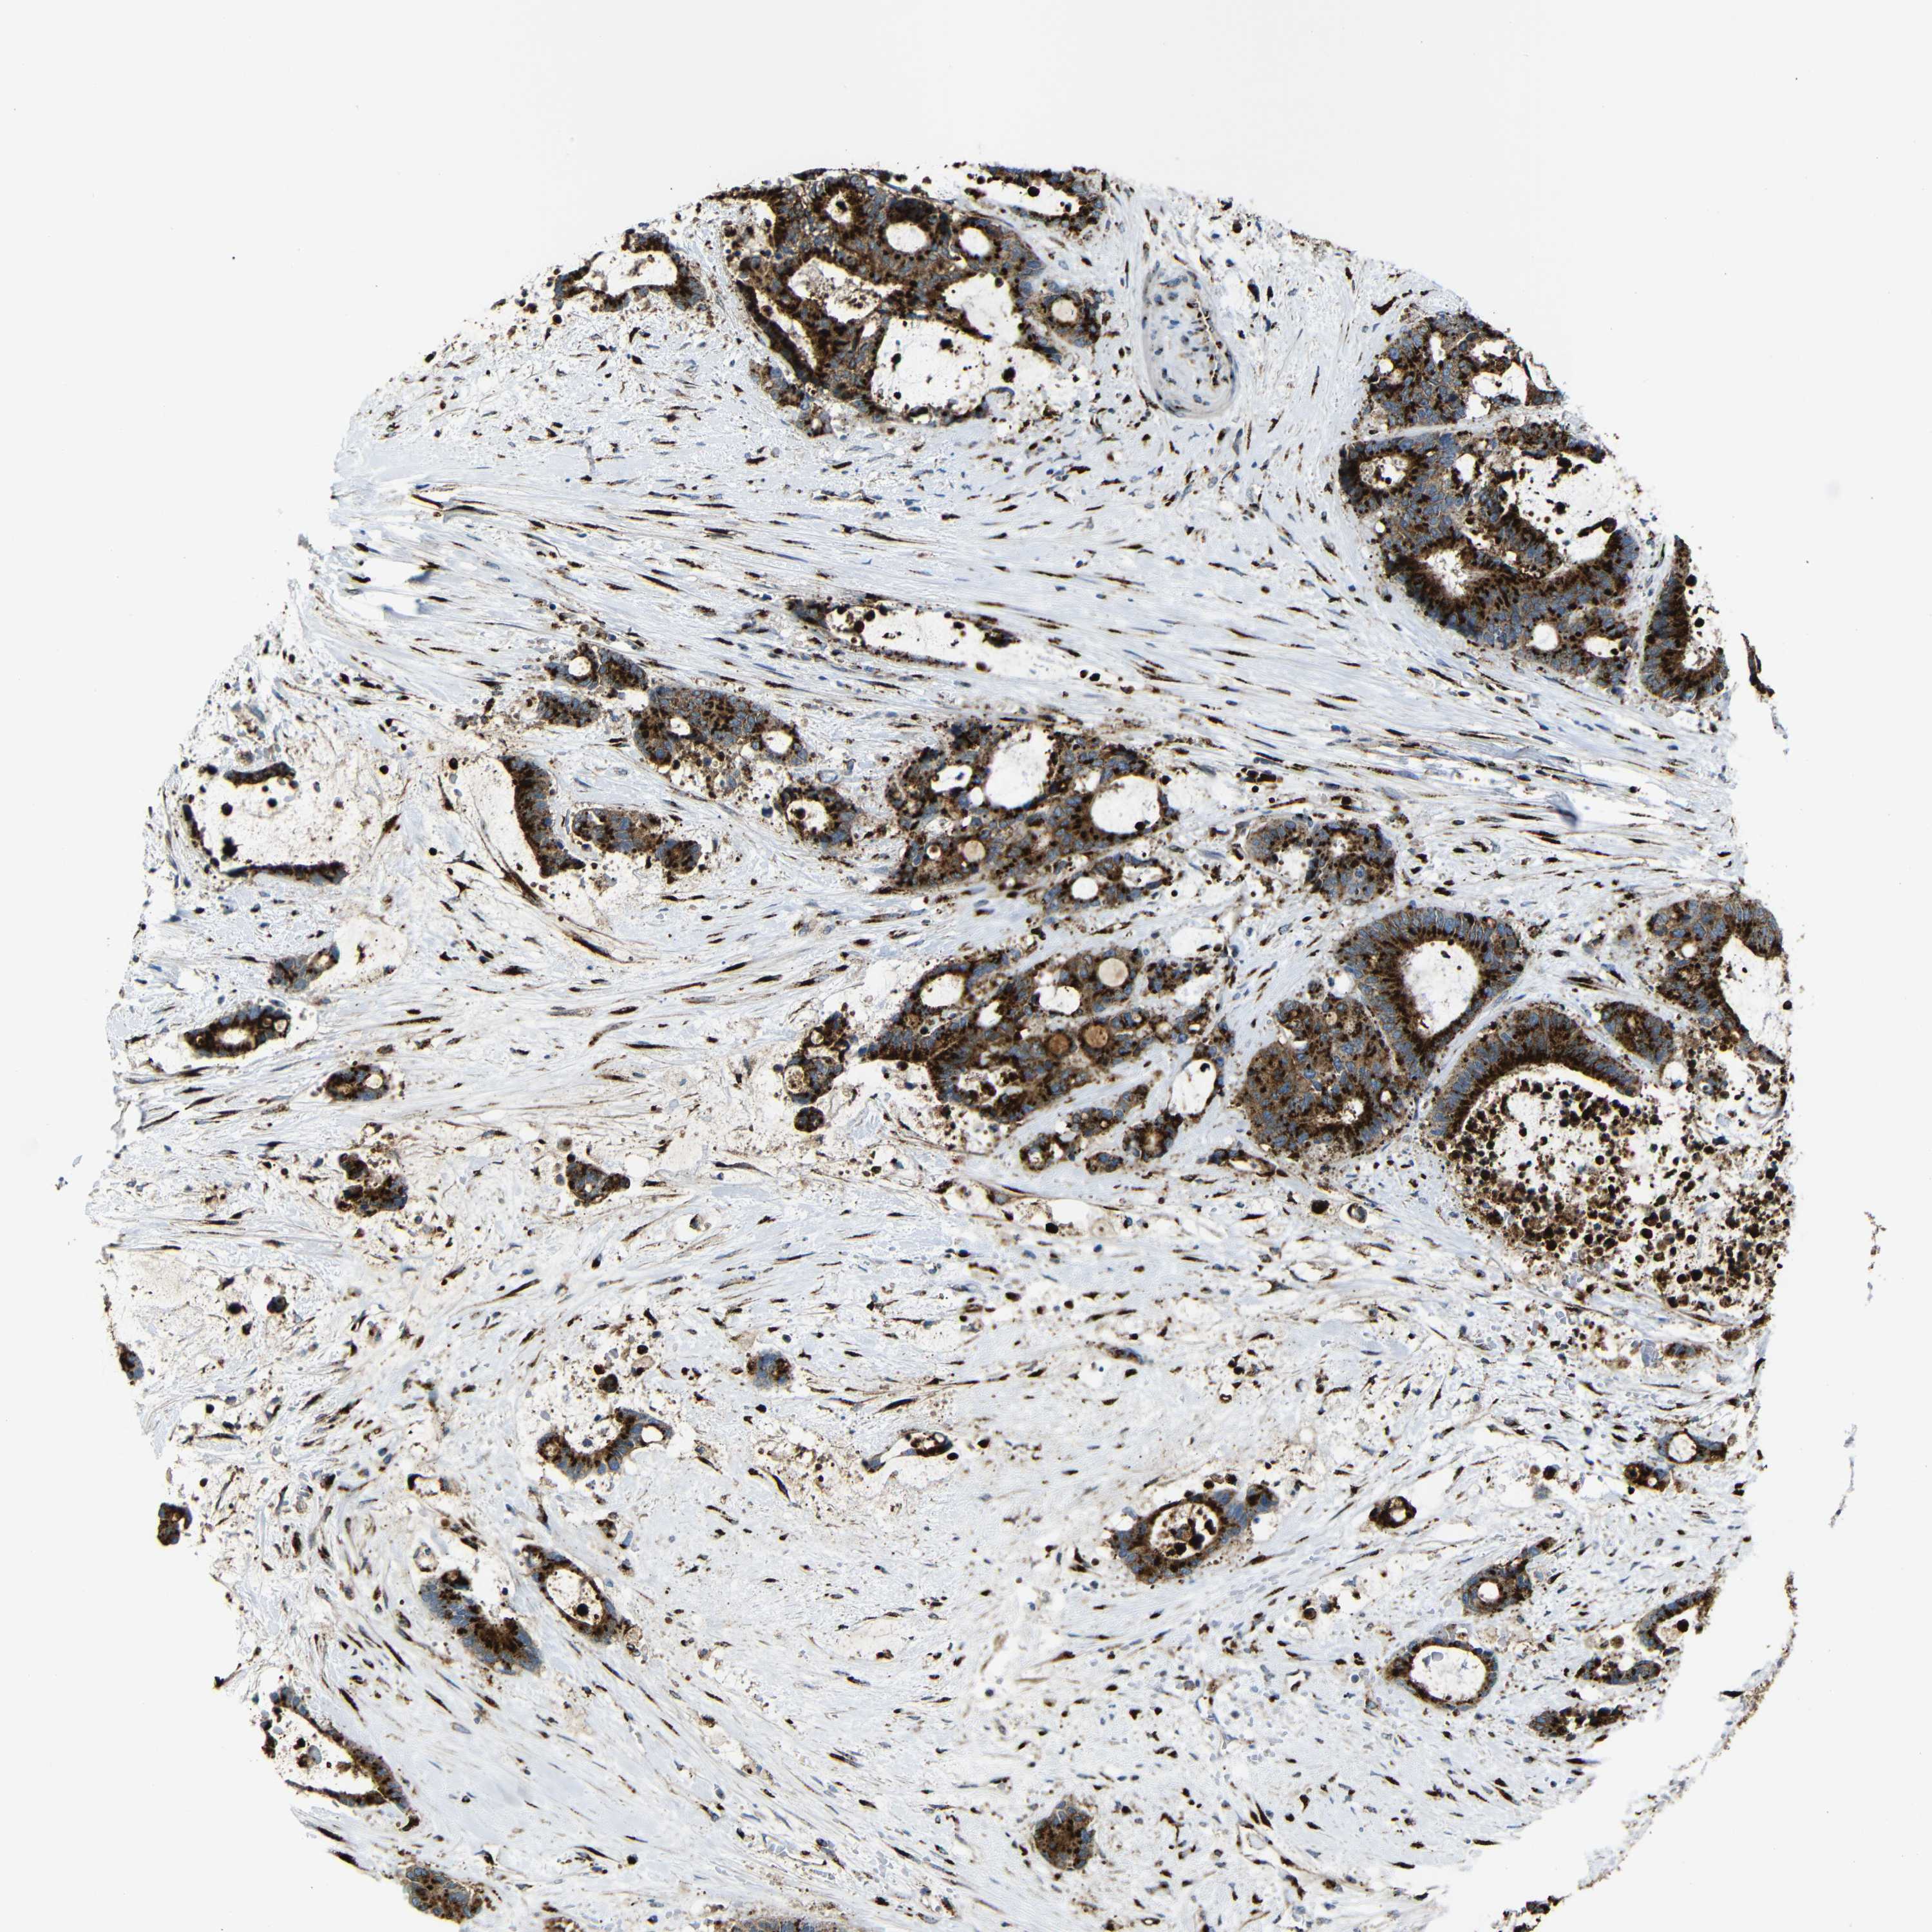

LIVER CANCER - Protein expressioni

A mouse-over function shows sample information and annotation data. Click on an image to view it in a full screen mode. Samples can be filtered based on level of antibody staining by selecting one or several of the following categories: high, medium, low and not detected. The assay and annotation is described here.

Note that samples used for immunohistochemistry by the Human Protein Atlas do not correspond to samples in the TCGA dataset.

Antibody stainingi

Antibody staining in the annotated cell types in the current human tissue is reported as not detected, low, medium, or high, based on conventional immunohistochemistry profiling in selected tissues. This score is based on the combination of the staining intensity and fraction of stained cells.

Each image is clickable and will lead to virtual microscopy that enables deeper exploration of all samples and also displays staining intensity scores, fraction scores and subcellular localization as well as patient and tissue information for each sample.

Antibody HPA012609

Antibody HPA012723

Antibody CAB011489

Staining

High

Medium

Low

Not detected

Intensity

Strong

Moderate

Weak

Negative

Quantity

>75%

75%-25%

<25%

None

Location

Nuclear

Cytoplasmic/membranous

Cytoplasmic/membranous,nuclear

Cholangiocarcinoma

Carcinoma, Hepatocellular, NOS